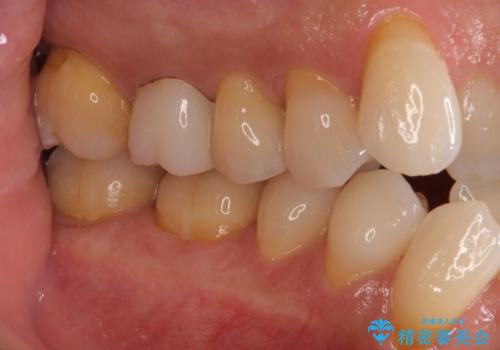

左上で効果を実感して頂き、その後右上もご希望されました。合計3本の歯を治療しました。

腫れもなくなり、見た目もきれいになったため、右上もご希望されて計3本の歯を治療しました。患者様には大変満足して頂きました。